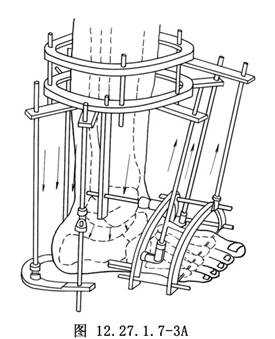

(1)“U”形截骨矯形術:用以改變整個足部與小腿及地面的相對位置關係,如圖示截骨經由距下關節,在後方通過跟骨上部,在前方穿越跗骨竇和距骨頸(圖12.27.1.7-3A)。“U”形截骨術可將足擺放在能踏平的位置而不破壞踝穴結構,使踝關節保持有限的動度。由於此截骨術穿越跗骨,存在距下關節僵硬是其前提條件。此截骨術可矯正蹠屈、跟骨內翻與外翻畸形,並改變足部高度,但不能矯正後足與前足之間的畸形。

(1)U形截骨矯形術:用以改變整個足部與小腿及地面的相對位置關係,如圖示截骨經由距下關節,在後方通過跟骨上部,在前方穿越跗骨竇和距骨頸(圖3.19.1.4-5)。U形截骨術可將足擺放在能踏平的位置而不破壞踝穴結構,使踝關節保持有限的動度。由於此截骨術穿越跗骨,存在距下關節僵硬是其前提條件。此截骨術可矯正蹠屈、跟骨內翻與外翻畸形,並改變足部高度,但不能矯正後足與前足之間的畸形。